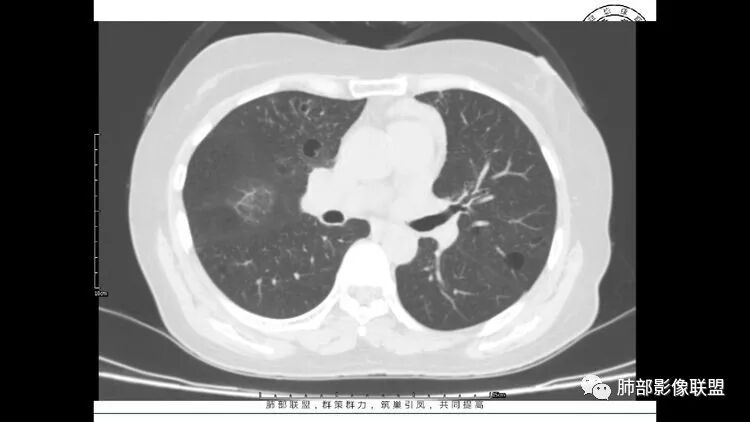

胸CT:1.双肺多发囊性变,以中下肺为主,病变边缘可见肺动脉,部分囊内可见分隔及肺动脉,双下部分肺野周围可见小叶中心结节及树丫征。

2 左肺上叶尖后段 右肺上叶前段 右肺下叶外基底段 结节影,边界清楚,可见柔软毛刺,左肺下叶后基底段混合密度影。

3.纵隔淋巴结肿大?,以主动脉弓为界向上向下增大。

患者中年女性,因右眼红痛1天就诊。胸CT:双肺多发囊性变及结节影,囊以中下肺为多,部分囊内可见分隔及肺动脉,结节部分为实性,部分为混合性,边缘光滑,未见明显毛刺、棘突、胸膜牵拉及血管集束征象。双中下可见支气管扩张及树丫征。淋巴结无明显肿大。综合考虑:一元淋巴细胞间质性肺炎。多元鉴别肺腺癌并转移等恶性病变。

左肺下叶混杂密度病灶,其内可见空泡,周围ggo清楚,考虑浸润性腺癌。双肺散在多发薄壁囊腔和实性结节,以胸膜下及血管旁分布位于,气囊可见血管贴边征,双肺小叶间隔及中央间质增厚,局部可见磨玻璃影及树芽征,纵隔内淋巴结肿大,考虑LIP

综上,考虑左下肺浸润性腺癌+LIP

LIP影像重要线索一句话:

双肺下叶分布为主的间质改变(磨玻璃影、小叶间隔增厚)、散在气囊影(常有血管贴边)、边界不清小结节